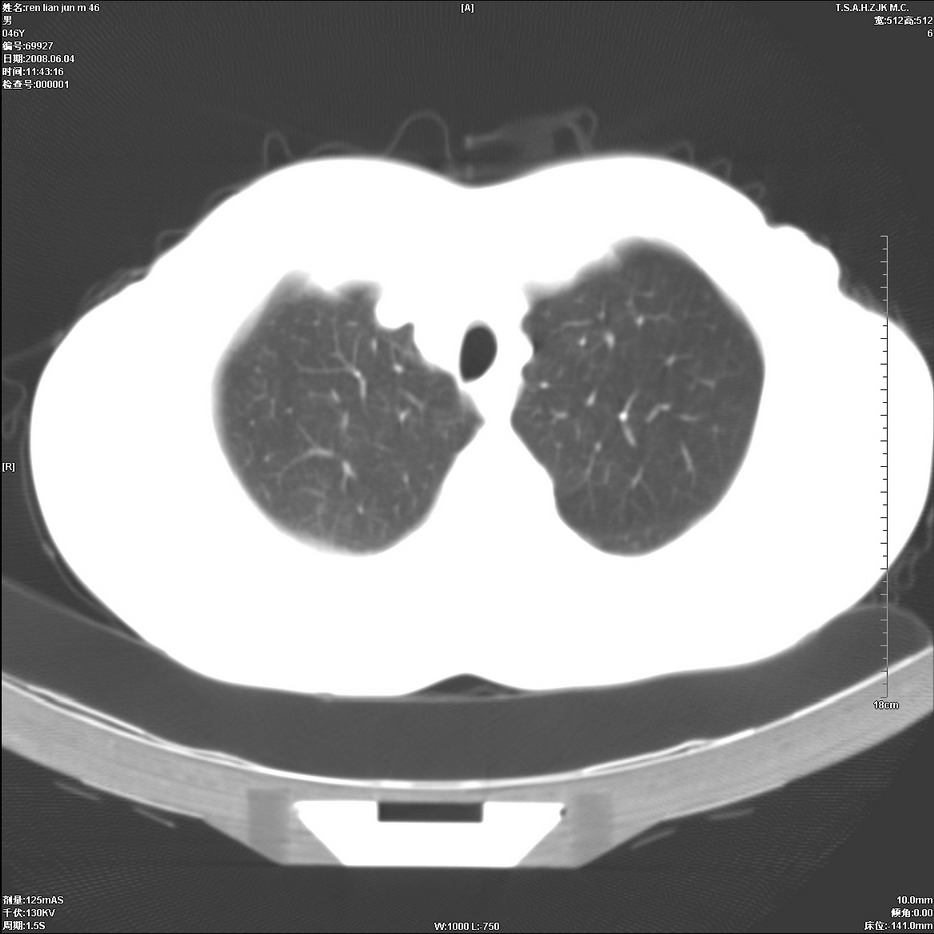

以下是引用qiu999在2008-6-5 17:14:00的发言:[br]考虑右肺中心型肺癌.颅内应做增强检查.

以下是引用形影不离在2008-6-5 19:18:00的发言:[br]右肺中心型肺癌并纵隔及左侧腋窝淋巴结转移,颅内应做增强检查。

以下是引用杀毒软件在2008-6-5 18:33:00的发言:[br]支持考虑右肺中心型肺癌,颅内病变是不是转移,不好说